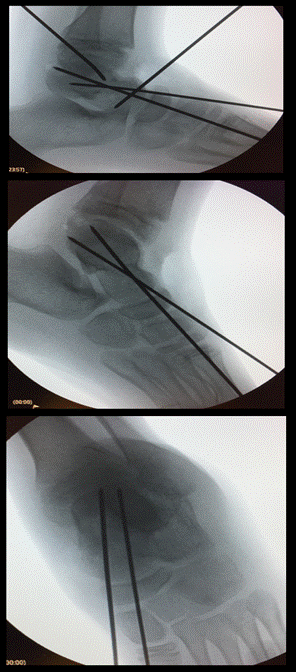

Se colocó manguito de isquemia, se realizó un abordaje longitudinal anterior y se incidió la cápsula longitudinalmente. Se redujo la fractura utilizando agujas de Kirschner como joystick hasta lograr una reducción anatómica. Posteriormente se fijó con 2 agujas de Kirschner paralelas anteroposteriores.

Fig. 3 Radiografías intraoperatorias. Reducción de fractura mediante kirschner. Fijación definitiva con 2 agujas de kirschner anteroposteriores.